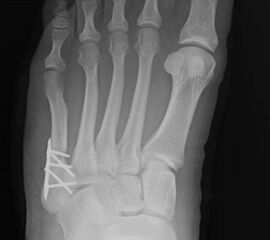

Abb. 12a: Typ III Deformität präoperativ im belasteten dp Röntgenbild.

Abb. 12b: Dorsoplantare Röntgenkontrolle nach medial schließender Osteotomie mit Schraubenosteosynthese.

Abb. 12c: Schrägaufnahme nach medial schließender Osteotomie mit Schraubenosteosynthese.

Abb. 12d: Seitliche Aufnahme nach medial schließender Osteotomie mit Schraubenosteosynthese.